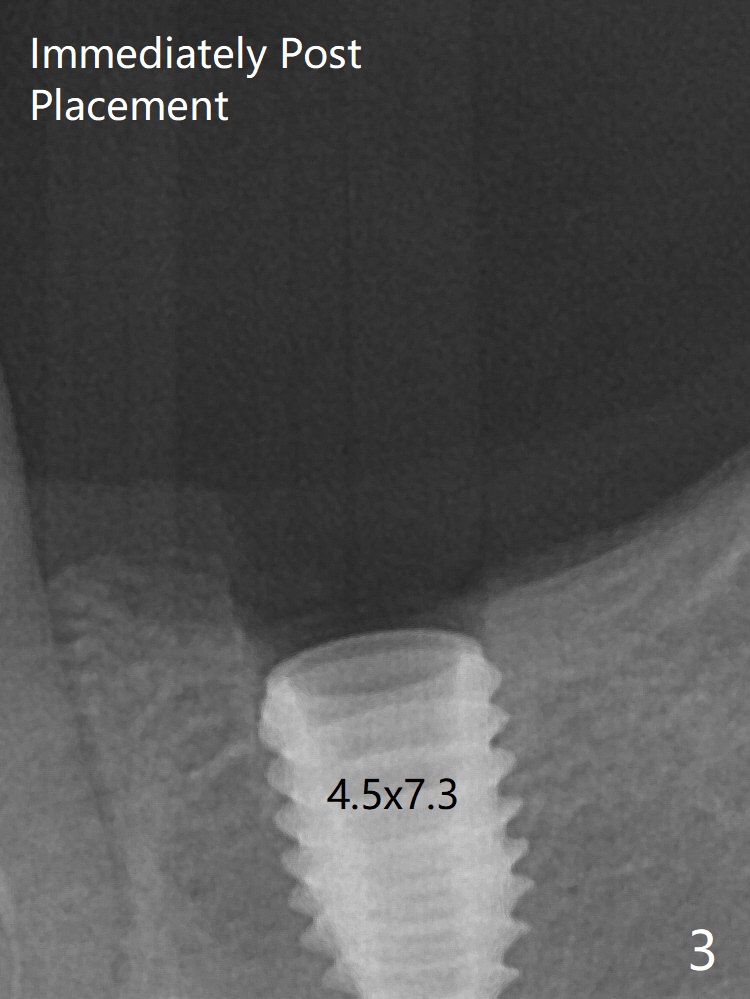

Fig.3: Implant placement at #19 with guide. The gingiva around the healing abutment (5.5x3 mm) at #19 is erythematous (Fig.5), probably related to the submerged abutment. There is no bone loss 5 months postop (Fig.6).